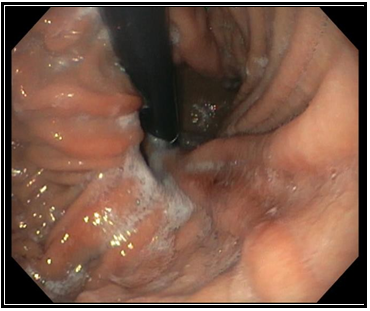

Oligosarcoma Arising from Oligodendroglioma-A case report